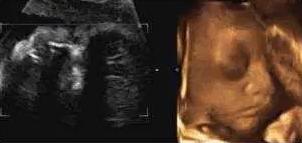

麻麻,我正在挠耳朵

【在妇产科医院,你可以看到这样的胎宝】